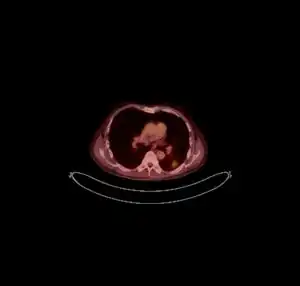

CT scan lungs: mass in right upper lobe

FDG PET/CT - Multiple nodules (some cavitating) in the left lower lobe